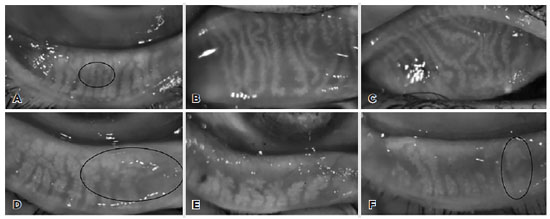

Comparisons of the morphological features of meibomian glands, percentage of the MG loss area, and meiboscore obtained on non-contact meibography are shown in table 2. Thickening, thinning, tortuosity, and the presence of ghost areas on the MGs were statistically significantly more common in the acne vulgaris group than in the control group (p=0.000, p=0.001, p=0.05, and p=0.006, respectively) (Figure 1). No significant differences in the fluffy areas and MG shortening were found between the groups (p=0.07 and p=1.0, respectively). The percentage of the MG loss area and meiboscore were significantly high in the acne vulgaris group on both upper and lower meibography (for the MG loss area on upper and lower meibographies, p=0.004 and p=0.002, respectively; for the upper and lower meiboscores, p=0.006 and p=0.000, respectively).

Figure 1. Non-contact meibography images of the upper (B, C) and lower eyelids (A, D–F) in the acne vulgaris cases: (A) thinning of the meibomian glands surrounded by a black circle; (B) tortuosity and thinning of meibomian glands and dropout area on the left side; (C) tortuosity in the meibomian glands greater than that depcited in image B; (D) ghost areas surrounded by a black circle; (E) marked meibomian gland loss area; and (F) thickening of a meibomian gland encircled with a black circle and meibomian gland loss.

In this study, we found that while the OSDI (p=0.01) and Oxford ocular staining scores (p=0.003) significantly increased in the patients with acne vulgaris patients, their Schirmer measurements (p=0.01) and invasive tear film breakup times (p=0.000) decreased. The MG secretion (p=0.000) and total eyelid scores (p=0.003), including telangiectasias, obstructed MG orifices, and anterior or posterior displacement of the mucocutaneous junction, were also increased in patients with acne. In a study by Özdemir et al., including 50 nodulo-cystic acne cases, they showed that abnormal tear film breakup times and Schirmer scores were significantly more common in the acne group than in the control group(7). The MG loss area and meiboscore were significantly higher in the acne group. Similarly to our finding, Muhafiz et al. claimed that tear breakup time was significantly lower (p< 0.001) and the loss rates in the MGs in both the upper (p=0.001) and lower eyelids (p<0.001) were greater in the acne group than in the control group(27). On the morhological evaluation of the MGs, thickening, thinning, tortuosity, and presence of ghost areas were statistically significantly more common in the acne vulgaris group than in the control group (p=0.000, p=0.001, p=0.05, and p=0.006, respectively). The fluffy areas and MG shortening also showed no significant difference between the groups (p=0.07 and p=1.0, respectively). Although we cannot explain these morphological changes completely, we considered that obstruction of the meibomian glands secondary to sebum overproduction and epithelital hyperkeratinization may cause increased tortuosity and thickening of meibomian glands. As the pathological process continues, thinning and ghost areas may occur. Future large-scale and more-comprehensive studies are worthwhile for establishing the importance of these morphological changes and how they can be useful in clinical practice.